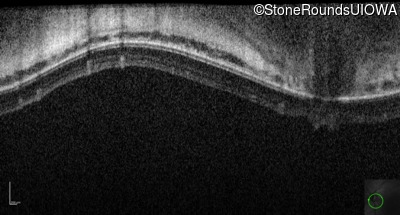

Optical Coherence Tomography - Left - 10/200 sc

Exemplar / OCT Stack